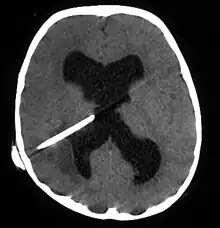

The diagnosis is established by a computed tomography (CT) (with contrast) examination. At the initial phase of the inflammation (which is referred to as cerebritis), the immature lesion does not have a capsule and it may be difficult to distinguish it from other space-occupying lesions or infarcts of the brain. Within 4–5 days the inflammation and the concomitant dead brain tissue are surrounded with a capsule, which gives the lesion the famous ring-enhancing lesion appearance on CT examination with contrast (since intravenously applied contrast material can not pass through the capsule, it is collected around the lesion and looks as a ring surrounding the relatively dark lesion). Lumbar puncture procedure, which is performed in many infectious disorders of the central nervous system is contraindicated in this condition (as it is in all space-occupying lesions of the brain) because removing a certain portion of the cerebrospinal fluid may alter the concrete intracranial pressure balances and causes the brain tissue to move across structures within the skull (brain herniation).

Ring enhancement may also be observed in cerebral hemorrhages (bleeding) and some brain tumors. However, in the presence of the rapidly progressive course with fever, focal neurologic findings (hemiparesis, aphasia etc.) and signs of increased intracranial pressure, the most likely diagnosis should be the brain abscess.